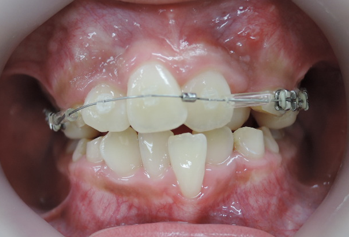

今回の症例は、悪い歯並びの代表例である八重歯です。

歯並びが悪いだけでなく、困ったことに犬歯から奥歯にかけて歯が嚙み合っていない開咬の状態です。

当院ではマルチループ(MEAW法)という上の写真で装着しているようなクネクネ曲がったワイヤーを使用して、上下の隙間を埋めていくことで歯並びを整えます。